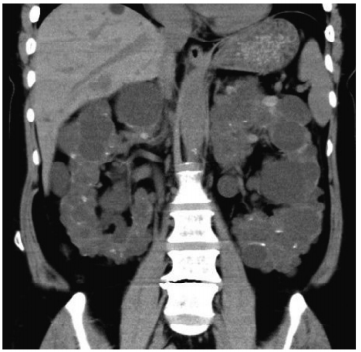

4 妊娠初期の経腟超音波像別冊No. 1 ①〜⑤を別に示す。 分娩予定日を決定するために有用な計測部位はどれか。 (A)① (B) ② (C)③ (D) ④ (E)⑤